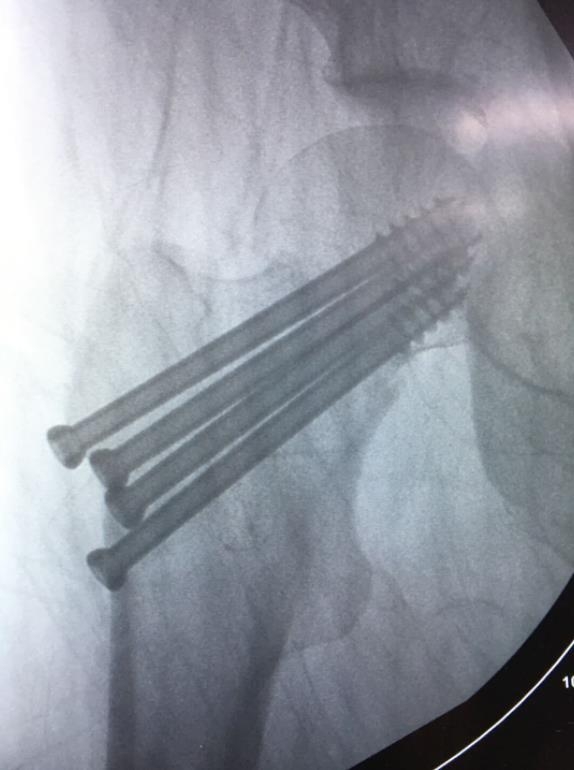

闭合复位经皮固定手术步骤

1、经皮沿股骨颈轴线置入空心钉导针,确保导针平行;

2、标准放置螺钉为倒三角形,其中下方螺钉在股骨矩,后方螺钉在后方骨皮质、研究发现倒三角形平行三枚螺钉能提供最佳的固定强度;

3、螺钉位于股骨颈四周,特别是后侧及下方,避免低于小转子方向进针,可能导致术后转子下骨折;

4、两个平面透视导针位置良好后切开皮肤,空心钻铭孔,导针引导下拧入空心钉,空心钉确保所有螺纹位于骨折线近端,螺钉头应距离软骨下骨5mm。

空心钉固定的三原则:“贴边、平行、倒品”

1、贴边是指3枚螺钉在股骨颈内,尽量靠近外围皮质。这样3枚螺钉作为一个整体,对整个骨折面可形成面状加压,如果3枚螺钉不够离散,更趋于点状加压,稳定性较差,不能较好地对抗扭转和剪切。

2、倒品有更明显的生物力学优势,CORR曾发表美国学者的一项生物力学研究,对比两种固定方式出现再骨折的负荷大小,发现倒三角再骨折的平均负荷11330N,而正三角仅7795N,差异明显,也就是说倒三角形固定可使再骨折的负荷提升45%。

图2 倒品字固定

3、平行生物力学更稳定。